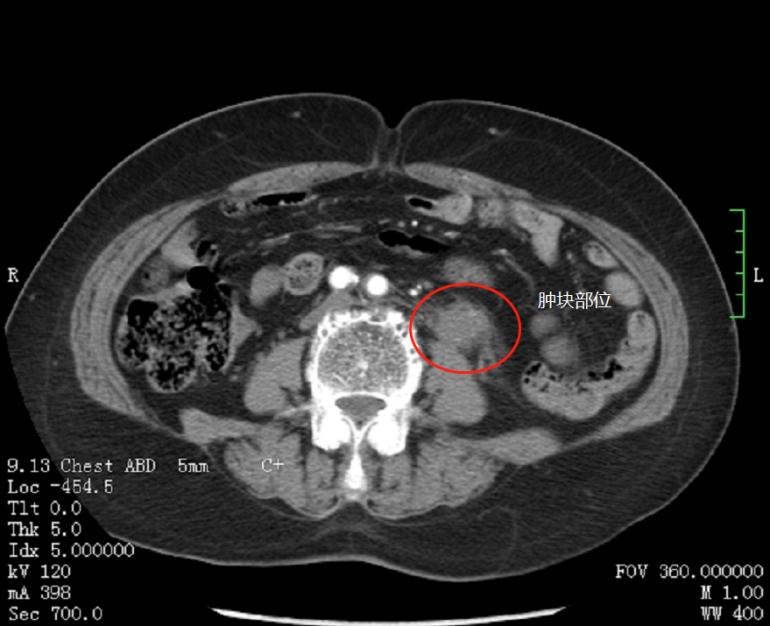

杨科主任安排为张奶奶做了相关检查,CT发现左侧输尿管上段增厚,肾脏严重积水。令人更加担心的是,通过肾功能检查,张奶奶左侧肾脏已经几乎无功能了。杨科主任团队结合张奶奶病史和检查结果,认为输尿管癌可能性大,为张奶奶制定了严密的手术方案。